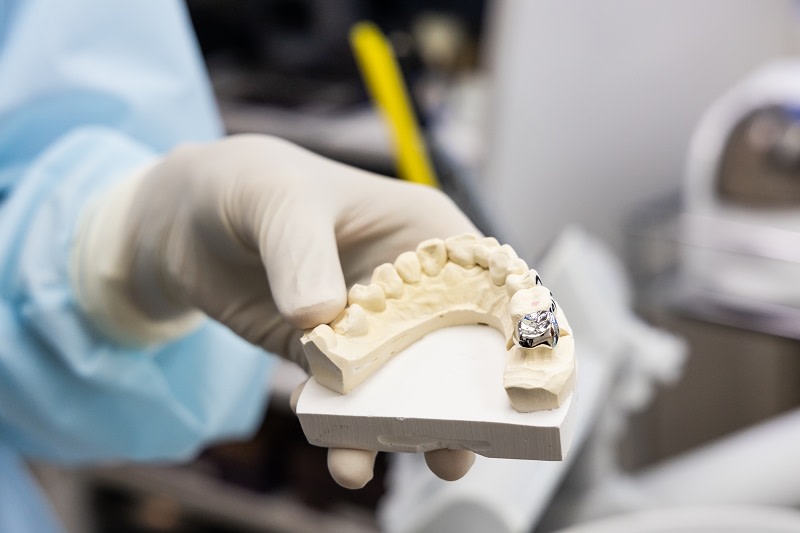

Die Krone wird in Spezial-Labors hergestellt